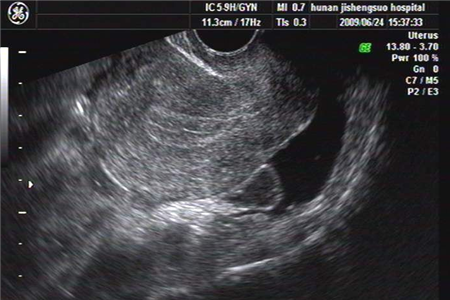

做阴超检查是不疼的,阴超只是一种超声检查方式,是把探头插入阴道进行检查的。

阴超指的是通过女性阴道进行的一种超声波检查,很多女性很害怕这个检查会造成疼痛的感觉,其实这个不用担心,只要阴道处没有伤口,一般是不会有明显的的痛感的。在进行检查之间,医生会在探头上涂抹润滑油,还会加上一个避孕套,所以不要紧张就不会感觉到痛。

阴超探头是圆柱形的,直径约2厘米,表面比较光滑,末端是圆形的,做检查时,探头的表面套上已消毒的乳胶套,一般用避孕套,套上都有润滑剂,插入阴道约10厘米后,就可以显示子宫和附件的图像了。阴超特别适合检查盆腔脏器的病变,比经腹部超声图像清晰,患者也不用憋尿,医生的手法都比较轻柔,患者不会感到痛苦。